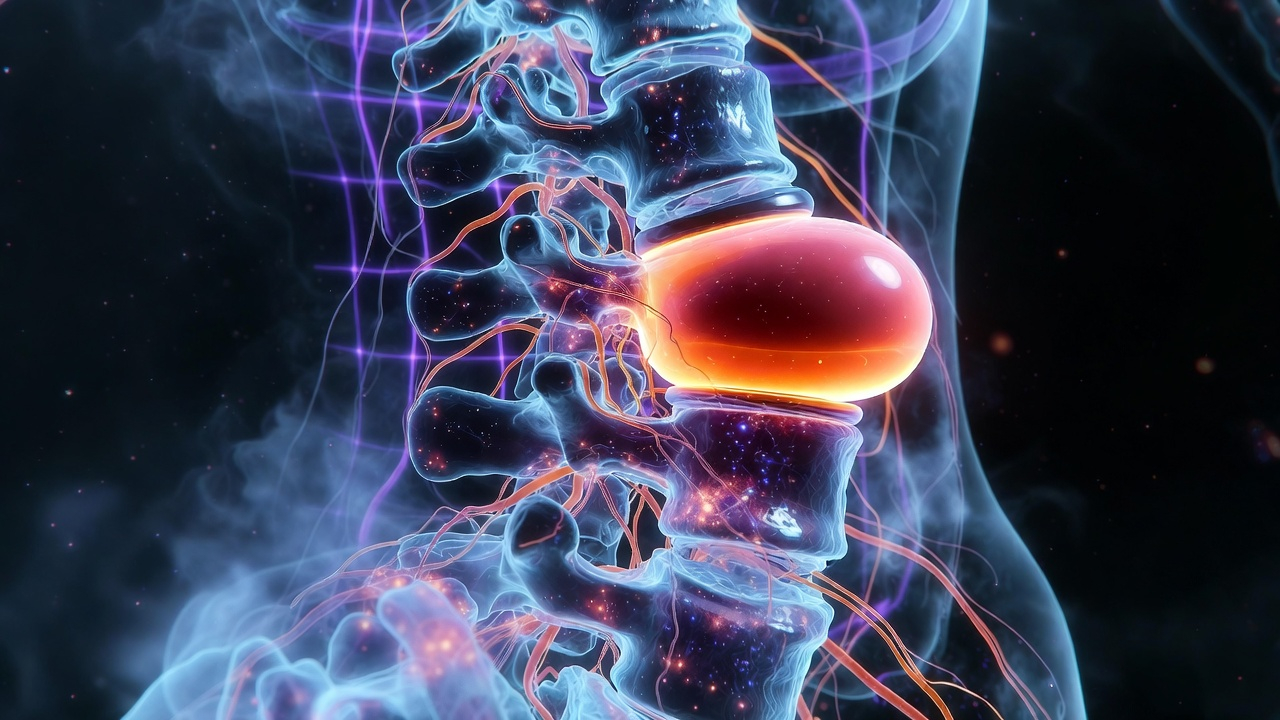

আমাদের মেরুদণ্ড অনেকগুলো ছোট ছোট হাড় (Vertebra) দিয়ে গঠিত। এই হাড়গুলোর মাঝখানে রাবারের মতো নরম ও স্থিতিস্থাপক একটি অংশ থাকে যাকে বলা হয় Intervertebral Disc। এই ডিস্কগুলো অনেকটা শক অ্যাবজর্বার (Shock Absorber) হিসেবে কাজ করে, যা হাঁটাচলা বা দৌড়ানোর সময় মেরুদণ্ডকে ধাক্কা থেকে রক্ষা করে।

যখন কোনো কারণে এই ডিস্কের ভেতরের জেলির মতো অংশটি (Nucleus Pulposus) বাইরের আবরণ ছিঁড়ে বের হয়ে আসে এবং মেরুদণ্ডের স্নায়ুর (Nerve Root) ওপর চাপ সৃষ্টি করে, তখনই তাকে PLID বলা হয়।

- MRI (Magnetic Resonance Imaging): PLID নির্ণয়ের জন্য সবথেকে কার্যকর পরীক্ষা। এর মাধ্যমে ডিস্কের অবস্থান এবং স্নায়ুর ওপর চাপের পরিমাণ স্পষ্টভাবে বোঝা যায়।